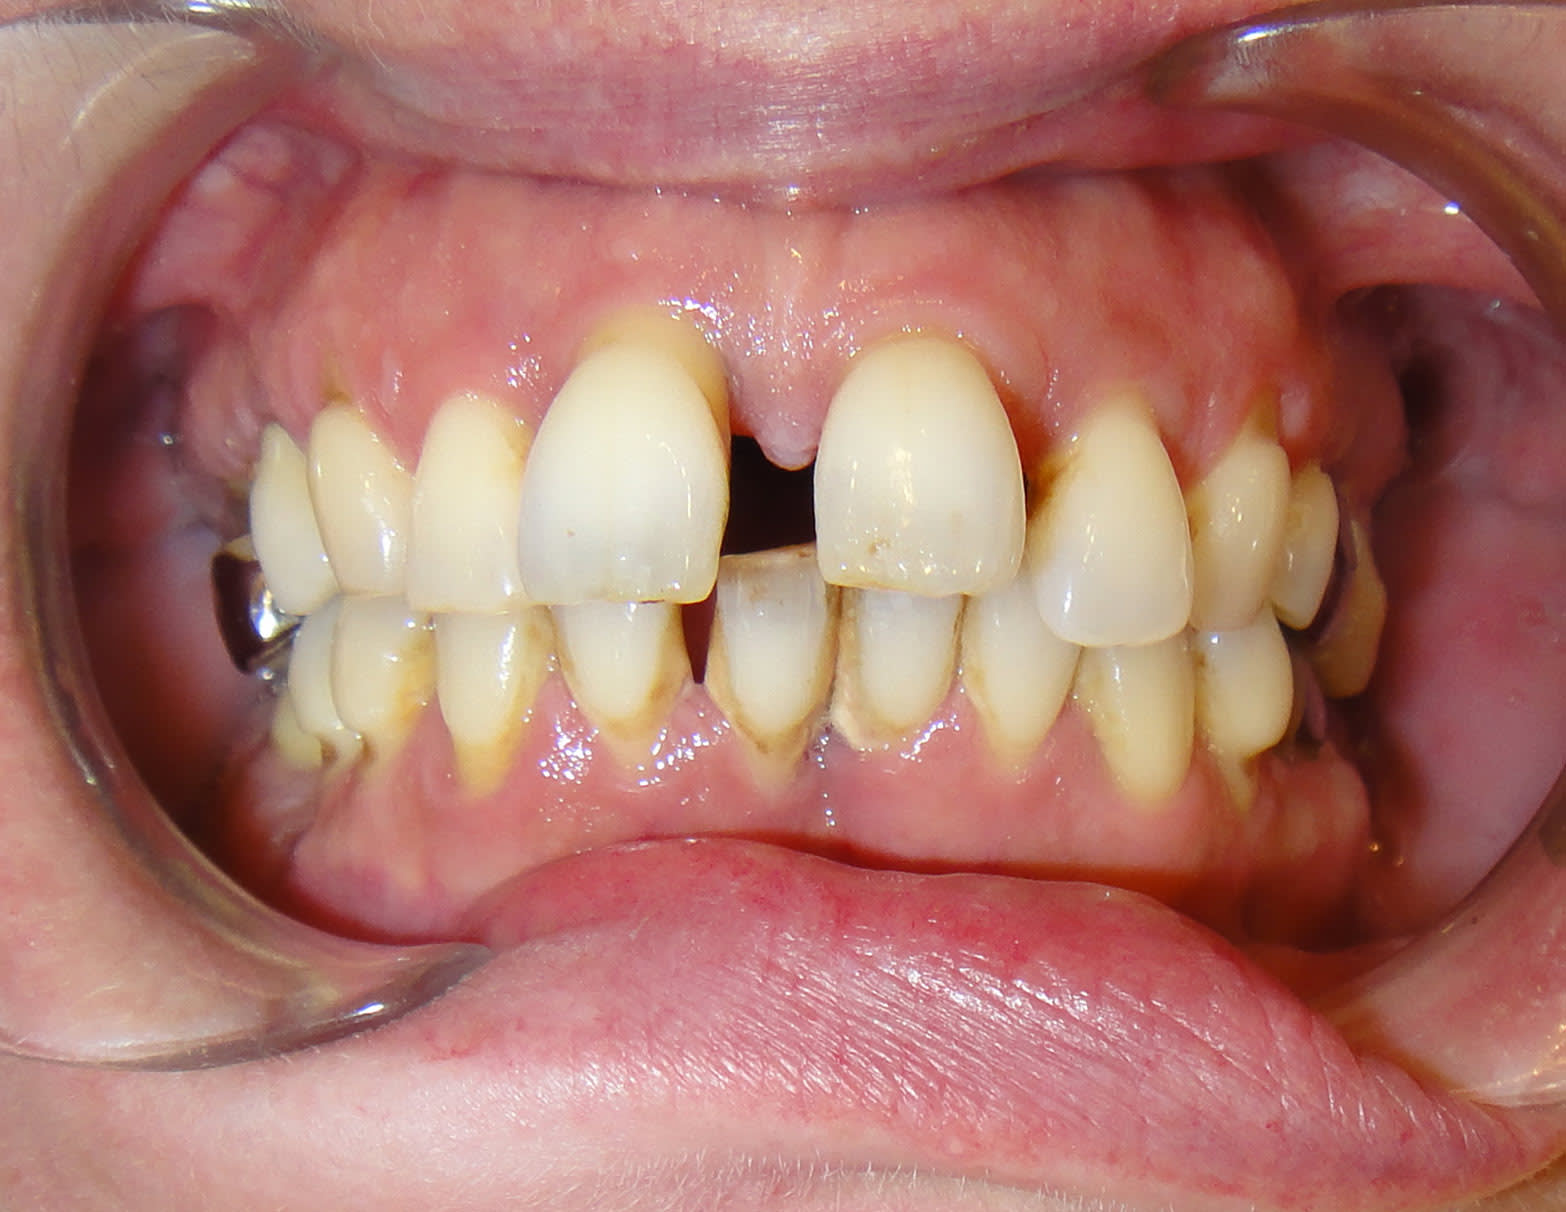

Toujours du tabac à gogo et une hygiène bof bof. Je fais 3 couronnes solidarisées 15 16 17 et un stellite haut .

Le stellite est réalisé avec 11 21 22 et un gros diastème qui lui plait plus.

Elle ne veut pas qu'on remplace les dents du bas.